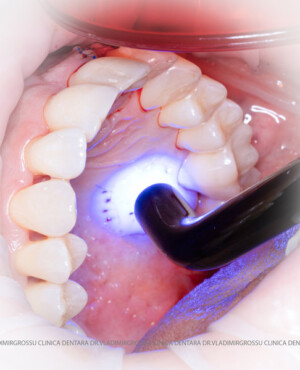

Un element esențial în procedura de aditie osoasă este utilizarea membranelor biologice, care izolează materialul osos de țesuturile moi (gingie) pe durata procesului de vindecare. Cele mai recomandate sunt membranele resorbabile din colagen sau pericard.